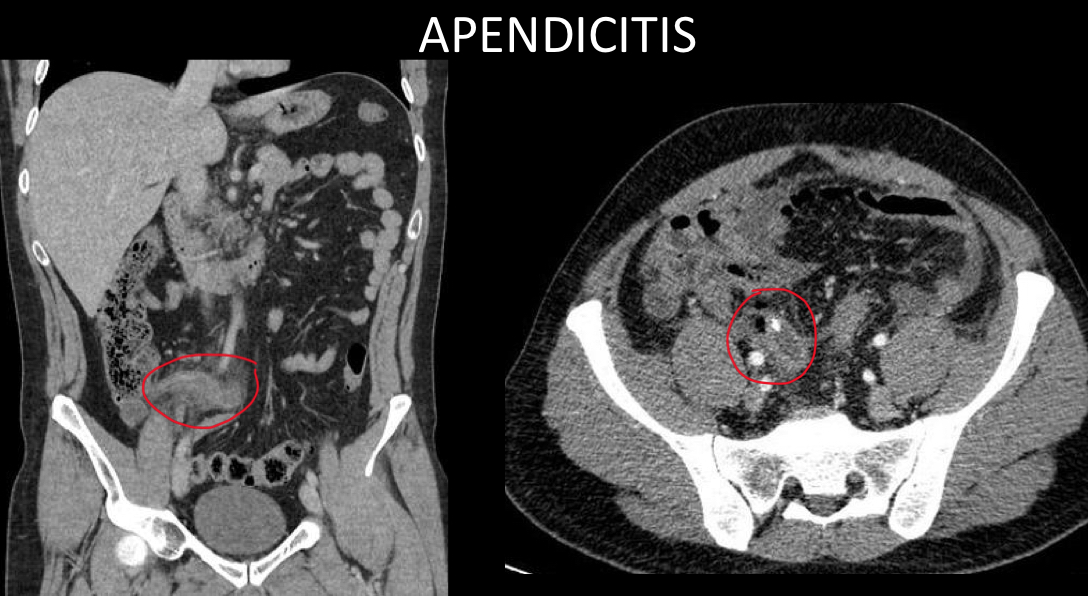

Lo mejor para apendicitis x imagen

la tc es mejor en

adultos

Apendice retrocecal

que se ve en tc

apendice distendida

Grasa sucia

Apendicolito

Realce con contraste

que otra cosa nos permite ver tc

absceso

Perforacion